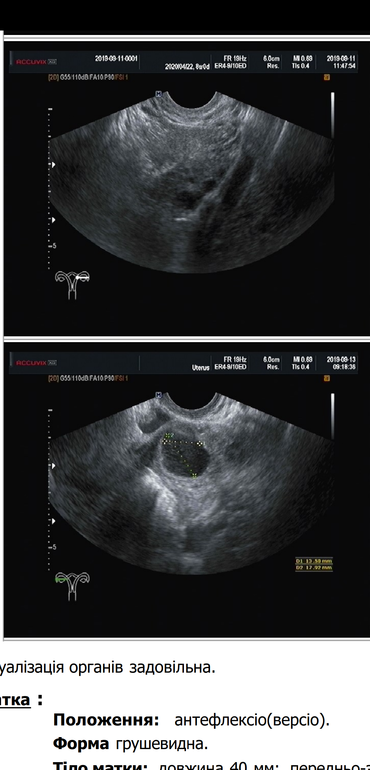

Сегодня 17 дц, врач сказала, что полноценная овуляция не произошла, может вышла яйцеклетка, а может нет, тк фолликул только немного надорвался... На 15 ДЦ был дф - 19 мм, а вечером сильно болел живот. Может у кого то и з вас была такая картина на УЗИ, чем закончилось? Я так устала ждать... И как назло моего мч часто не бывает рядом, раз в 3-4 месяца приезжает. Прошлый цикл была нормальная овуляция, только вот секса не было(((

Фото прилагаю